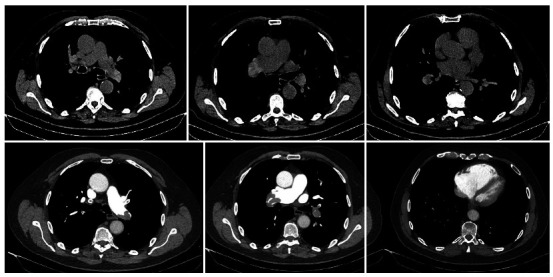

Life-threatening pulmonary embolism seen as hyperdense clots on unenhanced CT.

危及生命的肺栓塞,未增强CT表现为高密度血块。